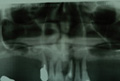

Q AQB T-type開発の背景を教えてください。 堤 AQBインプラントは、歯台部における再結晶化ハイドロキシアパタイトコーティング(以下HA) の骨伝導能による早期の骨結合で治療期間短縮を実現し、またツールを極力少なくすることで施術方法を簡素化し、仕様変更のない安定した扱いやすいシステムとして、国内有数のインプラントにまで成長しました。 1ピースタイプの発売から14 年経過し、その間にユーザーの先生から様々なご要望も届いています。 そのご要望のうち、「1ピースの術域を難症例にまで安全に拡大できたら、臨床により生かせる」という声を実現したのが、今回発売のT-typeなのです。

Q T-typeの特長を教えてください。 堤 従来のAQB1ピースを改良した形状で支台部にテーパー6°を付与しており、皮質骨と接するアバットメント部の径が約0.4 ?、通常サイズのものより太くなっています(左図) Q その改良の結果生まれたT-type固有の強みを教えてください。 堤 右表の3点がT-typeの特長でしょう。